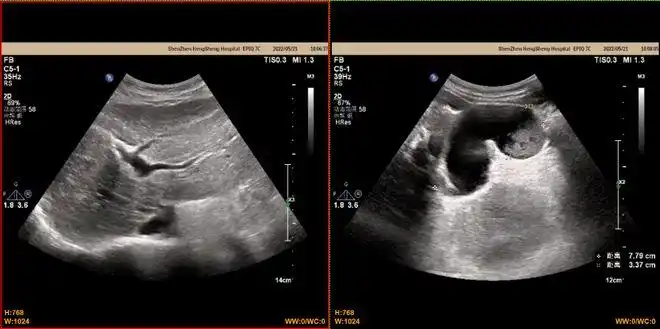

图2-4:腹部超声同时发现脾肿大,长径约16.7cm,厚约6.7cm.